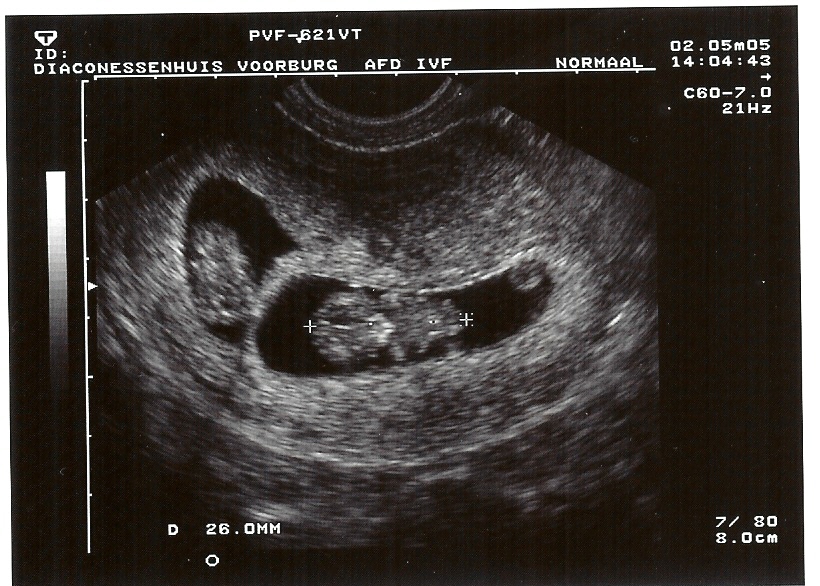

2-5-2005 Danique 9 weken, 4 dagen, 26mm